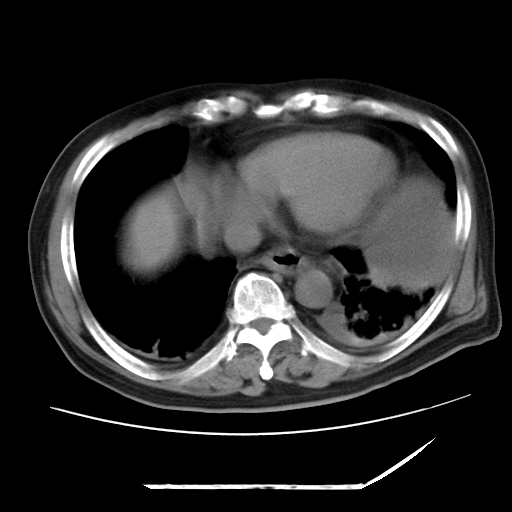

以下是引用zxl51642在2009-8-12 18:55:00的发言:[br]1、肠系膜脂肪浑浊,密度增高,腹水,支持腹膜炎诊断;2、右肾盂及输尿管中段结石,左输尿管起始段结石;3、胆囊切除术后改变?4、双侧胸膜腔少量积液;5、胰腺体积不大,勾勒清楚,肾前筋膜无增厚,不支持胰腺炎,请结合血尿淀粉酶及临床。